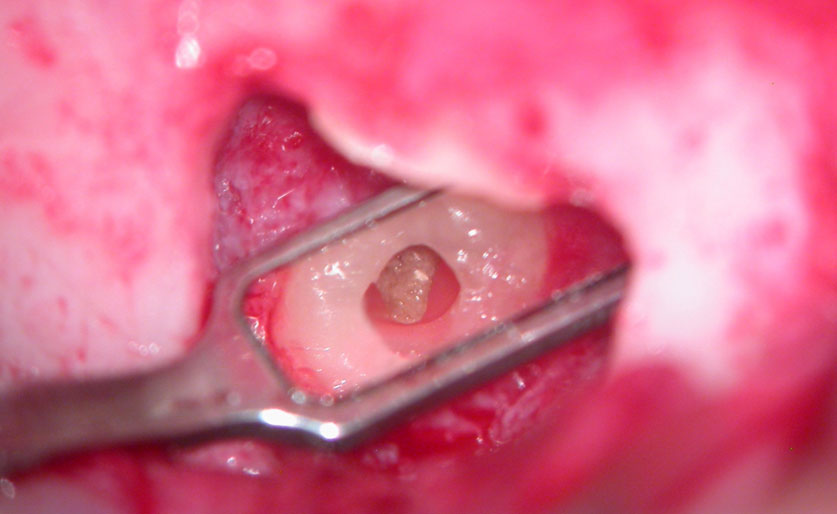

Before root-end resection

After initial root-end resection. Apical “Pouch” still unexposed

Further root resection and cleaning of the “Pouch”

Apical pouch filled with MTA

Post-Op